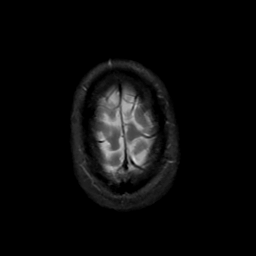

MR Study #20 October 6, 1991 -- Slice #46

[Home][Help][Clinical][Tour 1][Tour 2] Slice 46